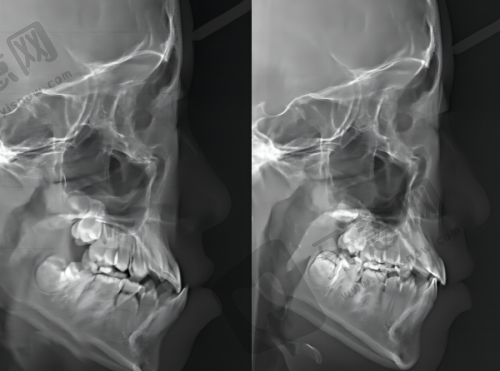

牙齿矫正:个性化方案定制,专精医生跟踪 合肥贝杰口腔医院的正畸医生均拥有10多年临床经验,且都是专科医生。他们能根据顾客CT信息和具体需求,设计个性化正畸方案,确保每位患者得到更适合自己的治疗。在复诊过程中,杨松、张贤军、张昱晶等医生会根据患者牙齿移动情况和治疗进展,及时调整正畸方案,确保矫正成效至佳。他们的专精负责让患者在舒适环境中完成牙齿矫正,重拾自信笑容。